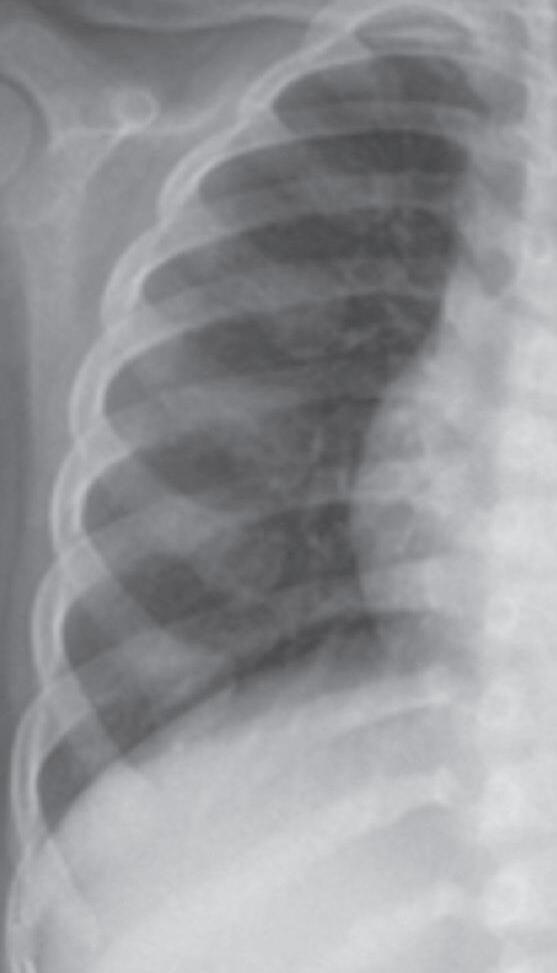

A história típica de uma criança ou adolescente com raquitismo traz relato de baixa velocidade de crescimento (VC) para a faixa etária, fraqueza muscular, dores ósseas, que podem ser demonstradas na forma de irritabilidade em crianças menores, fronte ampla, demora no fechamento das fontanelas em lactentes, alargamento das placas de crescimento em punhos, joelhos e tornozelos, deformidades em valgo e em varo nos membros inferiores. Podem-se observar, ainda, porém raramente e em condições clínico-laboratoriais mais graves, alargamento das junções costocondrais (rosário raquítico), retração do diafragma na altura do último arco costal (sulco de Har-

calcificação provisória na interface metáfise/epífise. Posteriormente, ocorre desorganização progressiva da placa metafisária, que se apresenta côncava, alargada, limites irregulares e franjeados, constituindo o sinal da taça (Figura 38.2).

Figura 38.2   (A a C) Achados radiológicos característicos em pacientes com raquitismo. Sexo feminino, 8 anos de idade, raquitismo calciopênico por deficiência da 25-hidroxilase (mutação no gene CYP2R1), observa-se alargamento das junções costocondrais (rosário raquítico) (A ). Sexo feminino, 2 anos de idade, raquitismo hipofosfatêmico ligado ao X (mutação no gene PHEX), observam-se rarefação óssea difusa, placas de crescimento dos membros superiores e inferiores com limites mal definidos, alargadas; metáfises distais do rádio e ulna com bordas côncavas (sinal da taça) e maior distanciamento entre metáfise e epífise (B e C)

Fonte: imagens pertencentes ao autor.